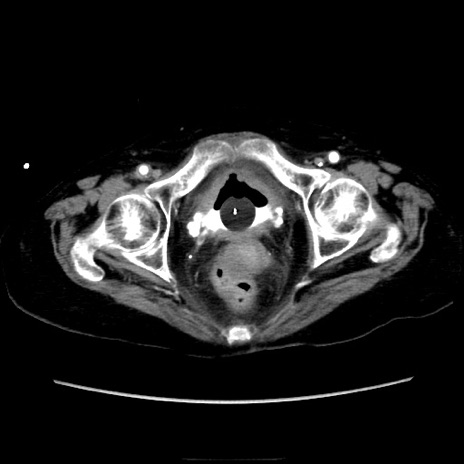

症例40(横断像)

【症例】90歳代女性

【主訴】腹痛・嘔吐

【現病歴】 食欲低下、嘔吐があり昨日他院受診。肺炎と診断され入院となる。入院後より腹部全体に圧痛あり。胃管留置され経過みていたが、症状持続するため、

当院転院となる。

【既往歴】胸椎圧迫骨折、胆石症

【身体所見】腹部:中央に激痛あり、圧痛あり、反跳痛不明

【データ】WBC 17100、CRP 18.82

横断像